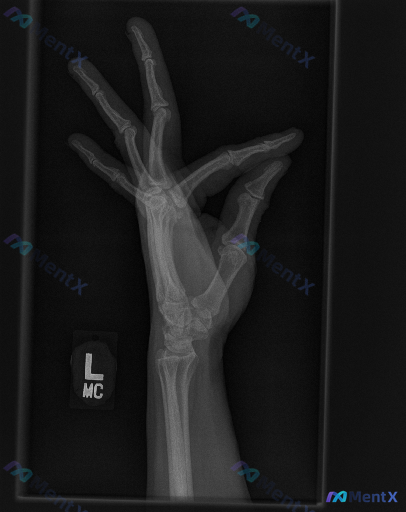

整理到一份右侧手部斜位X光片的影像资料与分析思路,想和大家讨论一下这类“影像看似正常,但可能有问题”的情况。 影像基础信息 - 投照体位:右侧手部斜位 - 显影质量:指骨、掌骨、腕骨结构显示清晰,曝光条件适中,骨皮质边缘与骨小梁均可分辨 直接影像学观察 - 骨皮质:逐一观察各手指及掌骨,未见明确中断...

整理到一组左手及腕关节斜位X光片的影像观察资料,想和大家讨论下判读思路与后续临床处理逻辑。 影像观察到的内容 1. 骨骼完整性:舟骨整体轮廓可见,骨皮质连续;头状骨、月骨、三角骨、豌豆骨、钩骨等其他腕骨,以及第1-5掌骨、各指骨骨质连续性均良好,未见明确骨折线、嵌插或骨小梁紊乱表现。 2. 关节对位...